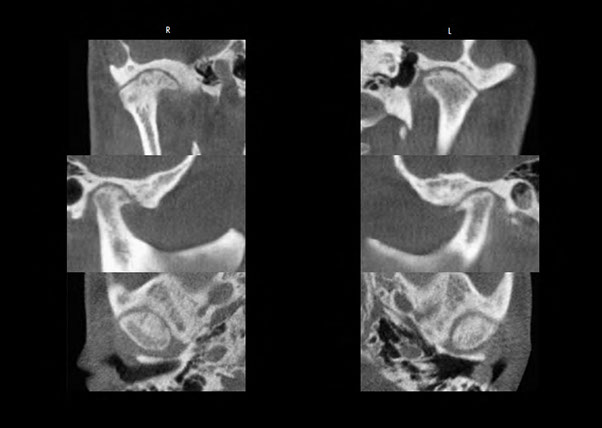

Osteoarthritis